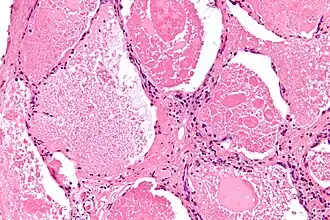

Micrografia com H&E mostrando glóbulos hialinos densos nas vias áreas.